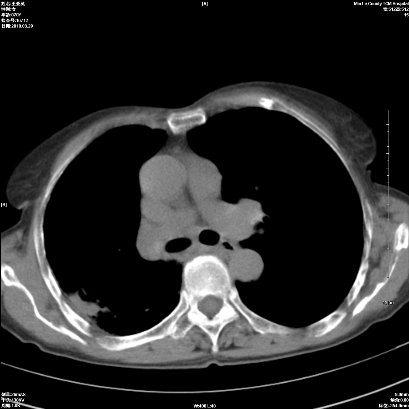

1 右肺门占位伴上叶不张 2 有肺多发感染 3 肝脏转移? 建议增强

1、右侧中央型肺癌伴右肺上叶不张建议支气管镜检   2、右肺中叶及下叶陈旧性病灶   3、肝内多发低密度影,肝内多发转移不除外,建议ct增强!

1)考虑右肺中央型肺癌伴右肺上叶肺不张,右肺门淋巴结转移;建议行支纤维镜检查。2)右肺中叶、下叶及左肺上叶舌段感染性病变。3)肝内多发低密度影,不排除转移瘤可能;建议行ct增强扫描检查。

ct所见:右肺上叶肺不张,呈软组织密度影向肺门区聚拢,其内可见含气段支气管及细支气管影,病灶内尚可见钙化结节。右肺上叶支气管狭窄,段支气管壁可见钙化。右肺下叶背段、右肺中叶见不规则小片絮状影及纤维条索影,形态较僵硬。右肺中叶胸膜旁可见多个小结节影。纵膈内见钙化淋巴结。

分析:右侧胸廓及右肺体积缩小,说明病变时间比较长了,应该是有数年的时间了,如果是短期内出现的肺不张,只会引起纵膈向患侧移位,而不会引起胸廓的塌陷。不张的肺组织内可见含气支气管影,说明右肺上叶支气管没有完全中断,只是狭窄。右肺中叶、下叶散在不规则病灶,部分呈纤维化改变。纵膈内的淋巴结大部分钙化。因此,本例给我的感觉良性病变的可能是大。

结论:考虑右肺上叶支气管内膜结核合并右肺上叶肺不张;右肺中叶、下叶陈旧性肺结核改变。